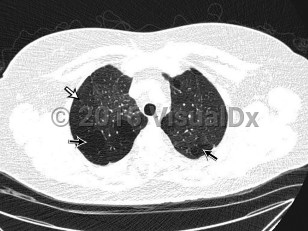

Bronchiolitis obliterans

The clinical syndrome manifests as an airway obstruction, cough, and slowly progressive dyspnea (weeks to months), with radiographic examination showing normal or hyperinflation of the lungs. Tachypnea, crackles, and/or wheezing may be evident on physical examination.